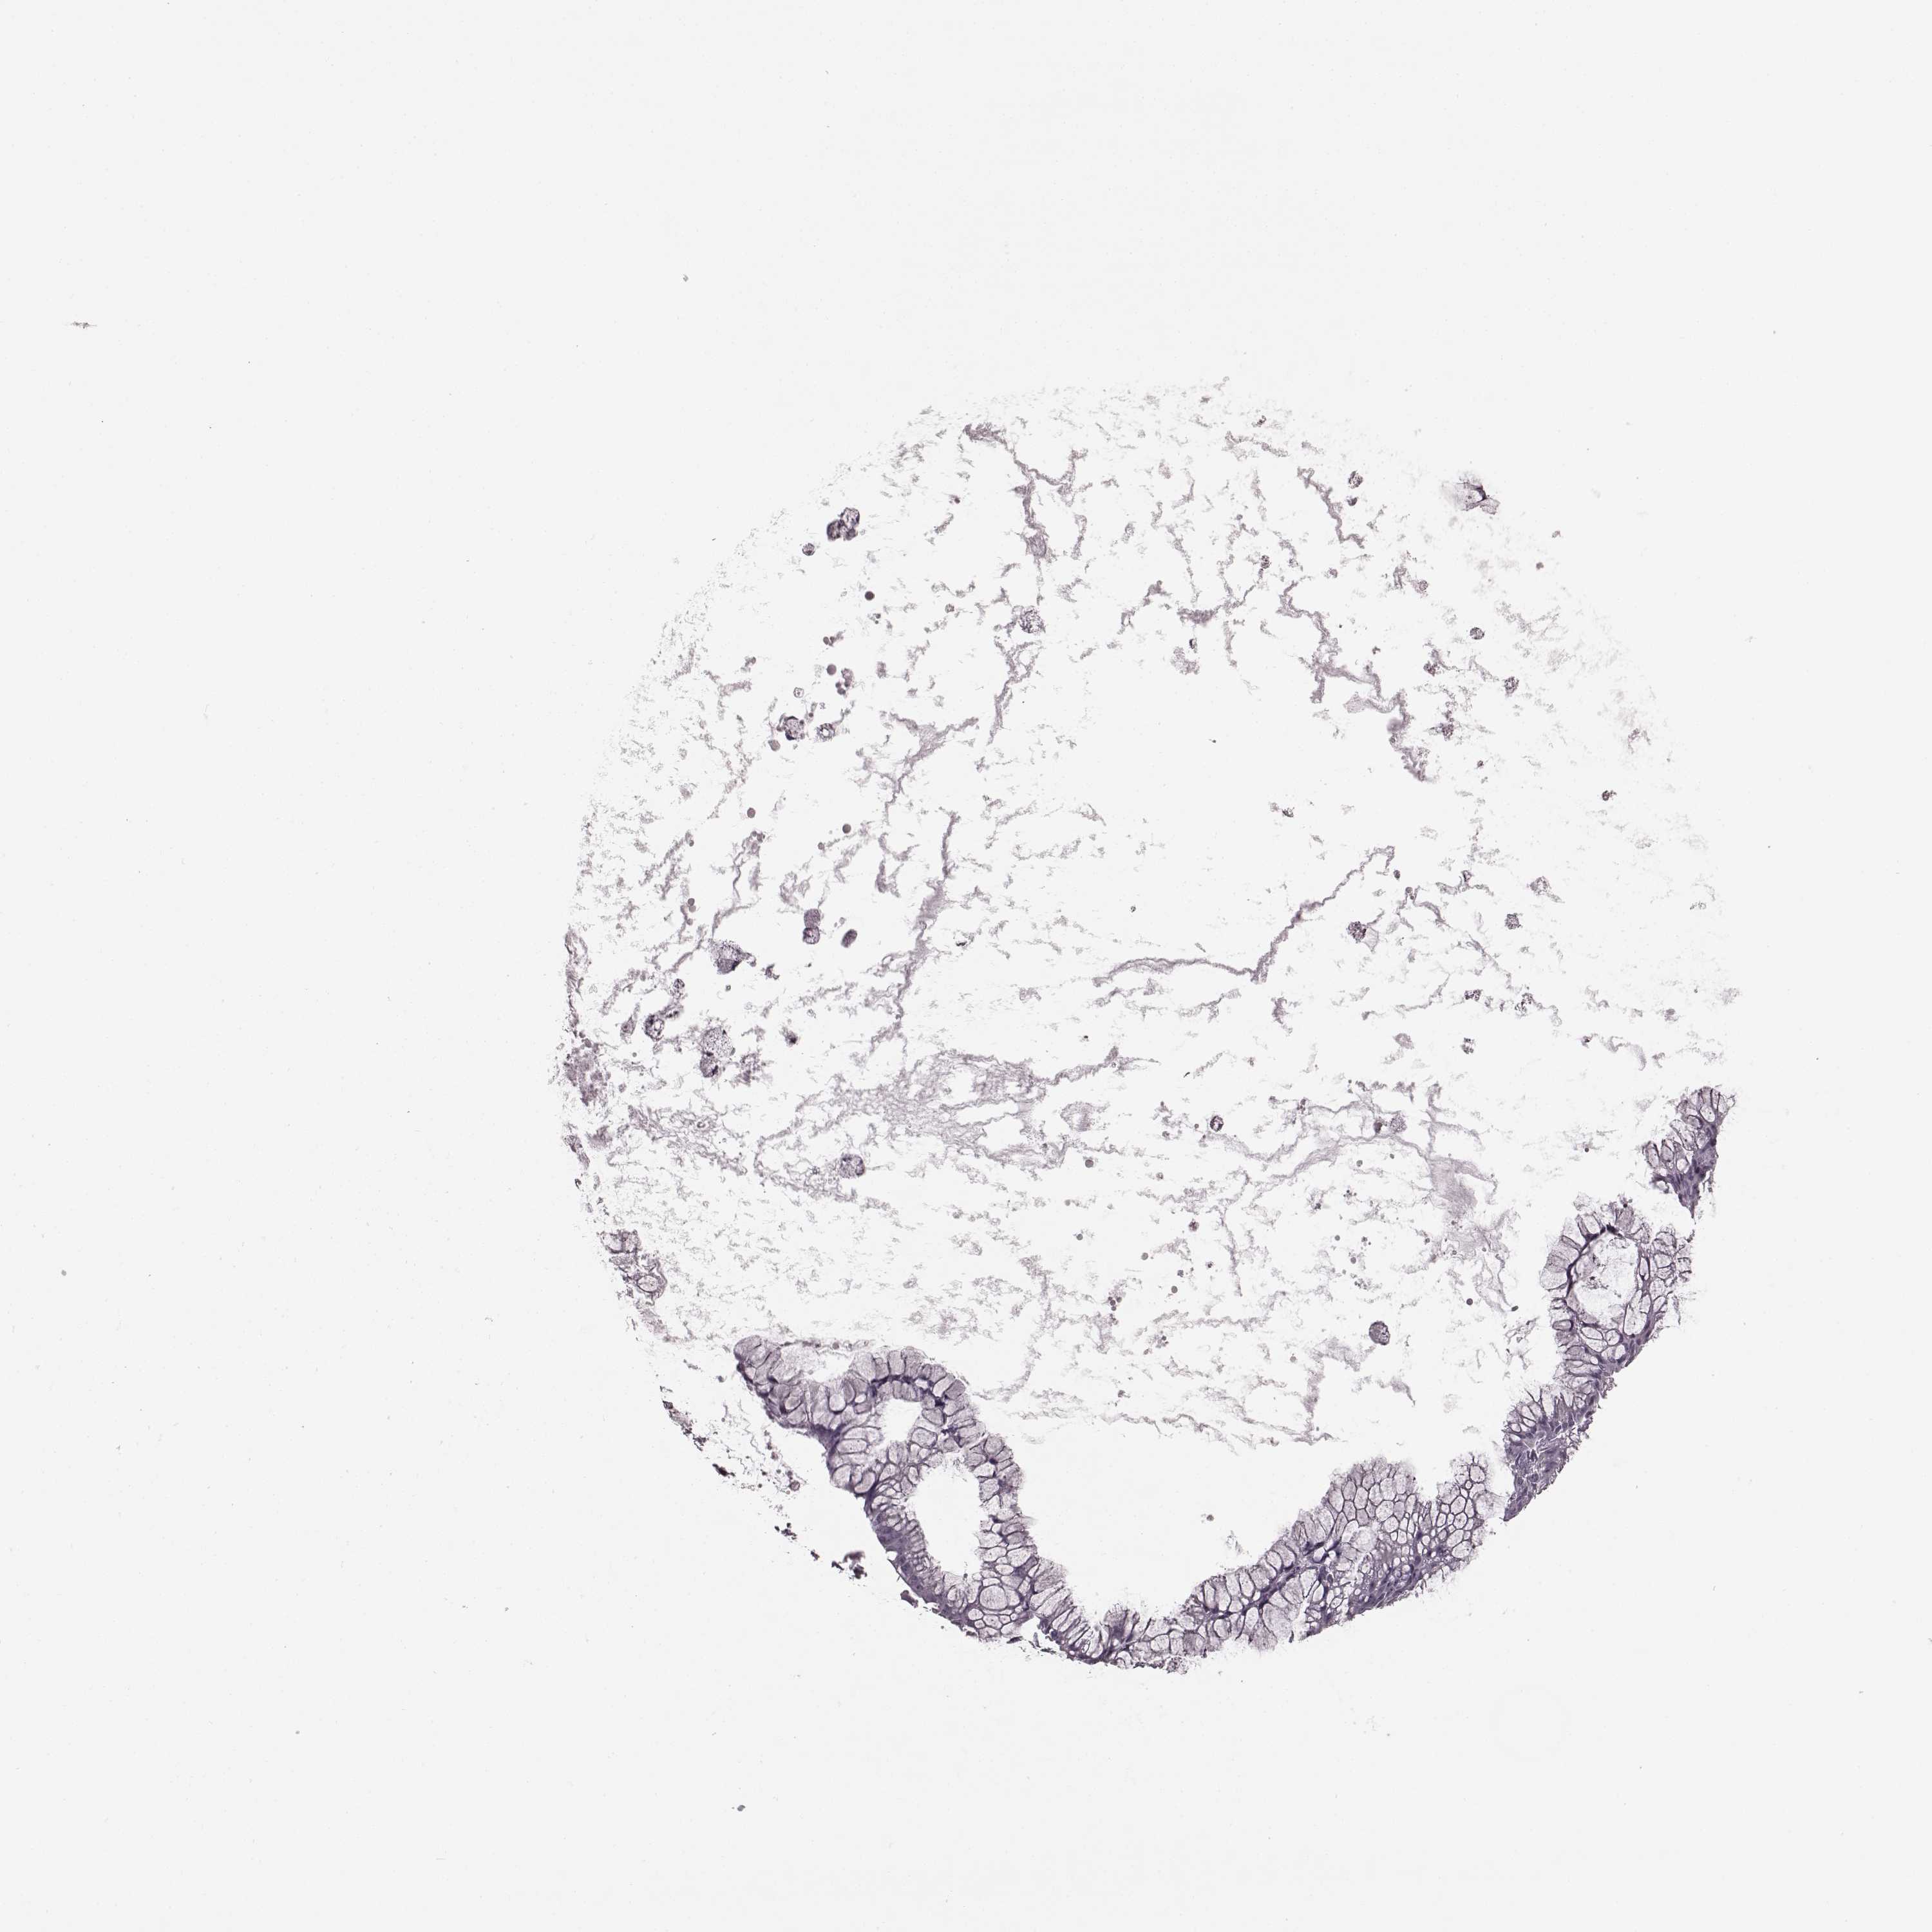

OVARIAN CANCER - Protein expressioni

A mouse-over function shows sample information and annotation data. Click on an image to view it in a full screen mode. Samples can be filtered based on level of antibody staining by selecting one or several of the following categories: high, medium, low and not detected. The assay and annotation is described here.

Note that samples used for immunohistochemistry by the Human Protein Atlas do not correspond to samples in the TCGA dataset.

Antibody stainingi

Antibody staining in the annotated cell types in the current human tissue is reported as not detected, low, medium, or high, based on conventional immunohistochemistry profiling in selected tissues. This score is based on the combination of the staining intensity and fraction of stained cells.

Each image is clickable and will lead to virtual microscopy that enables deeper exploration of all samples and also displays staining intensity scores, fraction scores and subcellular localization as well as patient and tissue information for each sample.

Antibody HPA014779

Staining

High

Medium

Low

Not detected

Intensity

Strong

Moderate

Weak

Negative

Quantity

>75%

75%-25%

<25%

None

Location

Nuclear

Cytoplasmic/membranous

Cytoplasmic/membranous,nuclear

Cystadenocarcinoma, serous, NOS

Cystadenocarcinoma, mucinous, NOS

Carcinoma, endometroid